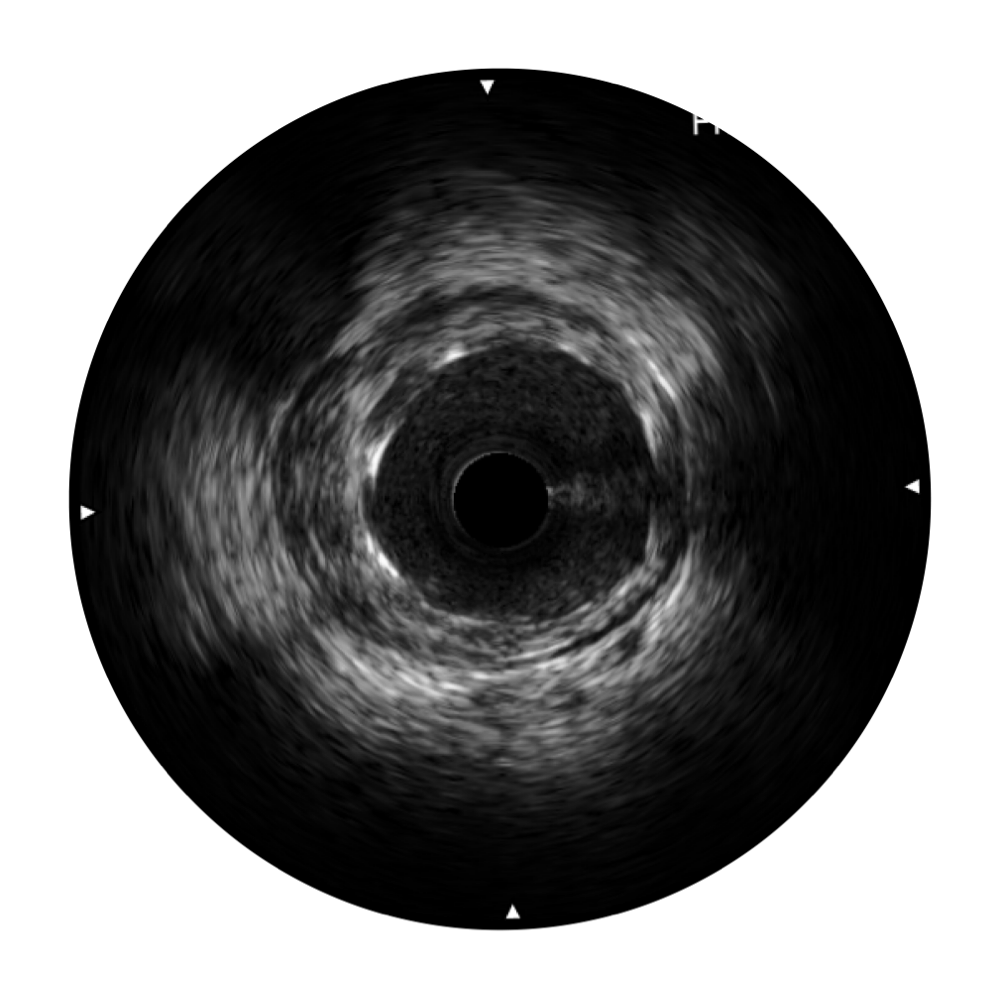

米兰官方网站宽频IVUS图像

传统IVUS图像

对比传统IVUS导管成像,米兰官方网站宽频IVUS图像的近场支架梁显影更细腻,远场中膜外血管仍清晰可辨,兼顾远中近,兼顾分辨力与穿透深度